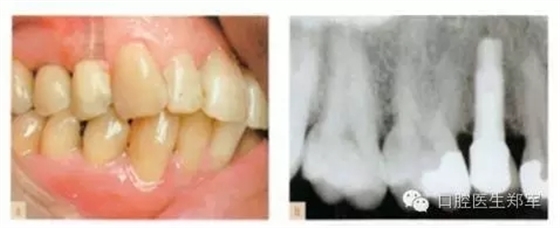

單顆牙缺失的種植體修復(fù):與自然牙齒修復(fù)相似,都是由咬合原則指導(dǎo)。種植體中心咬合接觸,咬合面減徑(如果可能的話),牙尖平坦(如果可能的話),全牙列在最大牙尖交錯時能夠同時接觸,以上這些都具備臨床和生物力學(xué)意義。修復(fù)體不應(yīng)該有非正中干擾,但是適當?shù)臅r候可以設(shè)計成部分選擇性非正中引導(dǎo)。(圖1和圖2)

圖1 a-b 單顆前磨牙種植、良好的接觸、同時全口咬合接觸、以種植體中心為咬合接觸點。 |

圖2 a-b 上頜第二前磨牙種植體支持式的牙冠,工作側(cè)由上頜頰尖的內(nèi)斜面引導(dǎo)。c-d 咬合紙染色部分是牙合干擾的地方,通過調(diào)磨直至恢復(fù)合適的工作引導(dǎo)(綠色箭頭部分)。